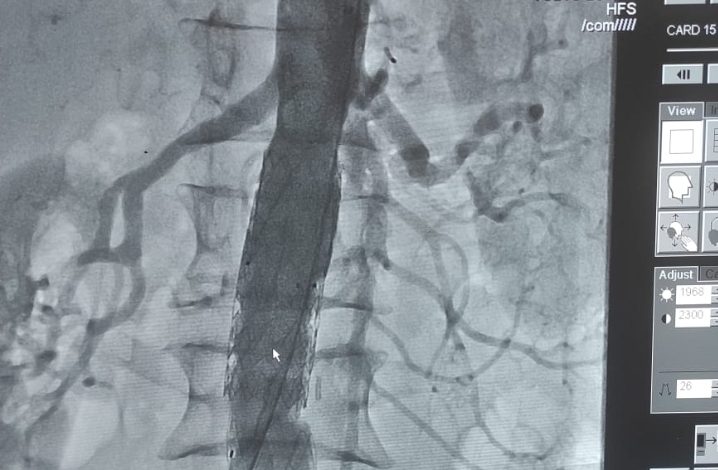

एक मरीज पर कार्डियोलॉजी विभाग के डॉक्टरों IGMC शिमला द्वारा percutaneous स्टेंट ग्राफ्ट का मामला पेश किया गया, जो कि चिरगाँव रोहड़ू से हैं। जो 66 पुरुष है और पेशे से किसान है।

यह मरीज पहली बार 31/12/20 को शिमला आया था, जिसमें पेट में दर्द और 5 दिनों की अवधि के बाद उसकी सर्जरी की गई थी, उसे सर्जरी विभाग में देखा गया था और सीटी पेट पर पेट की महाधमनी धमनीविस्फार पाया गया था, जो मुख्य धमनी का पतला होना था। यह खतरनाक है क्योंकि यह टूट सकता है और अचानक मौत का कारण बन सकता है।

इस मरीज को CTVS विभाग भेजा गया था, जहाँ पेट खोलकर सर्जरी का प्रयास किया गया था, लेकिन कुछ कारण से यह सफल नहीं था।

तब शल्यचिकित्सा विभाग ने सर्जरी के बिना धमनीविस्फार को बंद करने का प्रयास करने के लिए कार्डियोलॉजी विभाग में डॉ राजीव मारवाहा से संपर्क किया।

मामले का पुनर्मूल्यांकन किया गया और एक अन्य सीटी का प्रदर्शन किया गया और मामले की योजना बनाई गई।